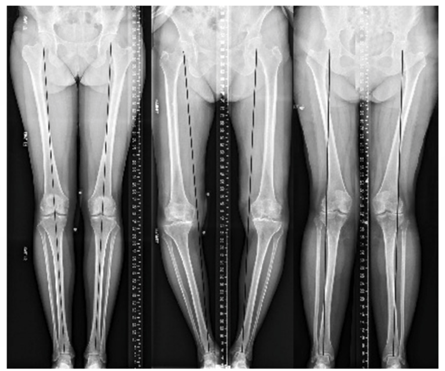

What are the different alignments of the knee and who do they most occur in?

Varus deformity – more common in sports players. Varus knee is associated with higher osteoarthritis.

Valgus deformity– more common in models/slim-women.

Neutral alignment – more common in desk job people.

What can be done surgically when someone has misalignment of the knee?

OSTEOTOMY

If younger than 40 then the bone can be cut across and hinnged open, and a growth plate added to straighten out the leg.

However, this is a procedure which requires 6 months rehabilitation after in a person that currently has nothing wrong with their joints.